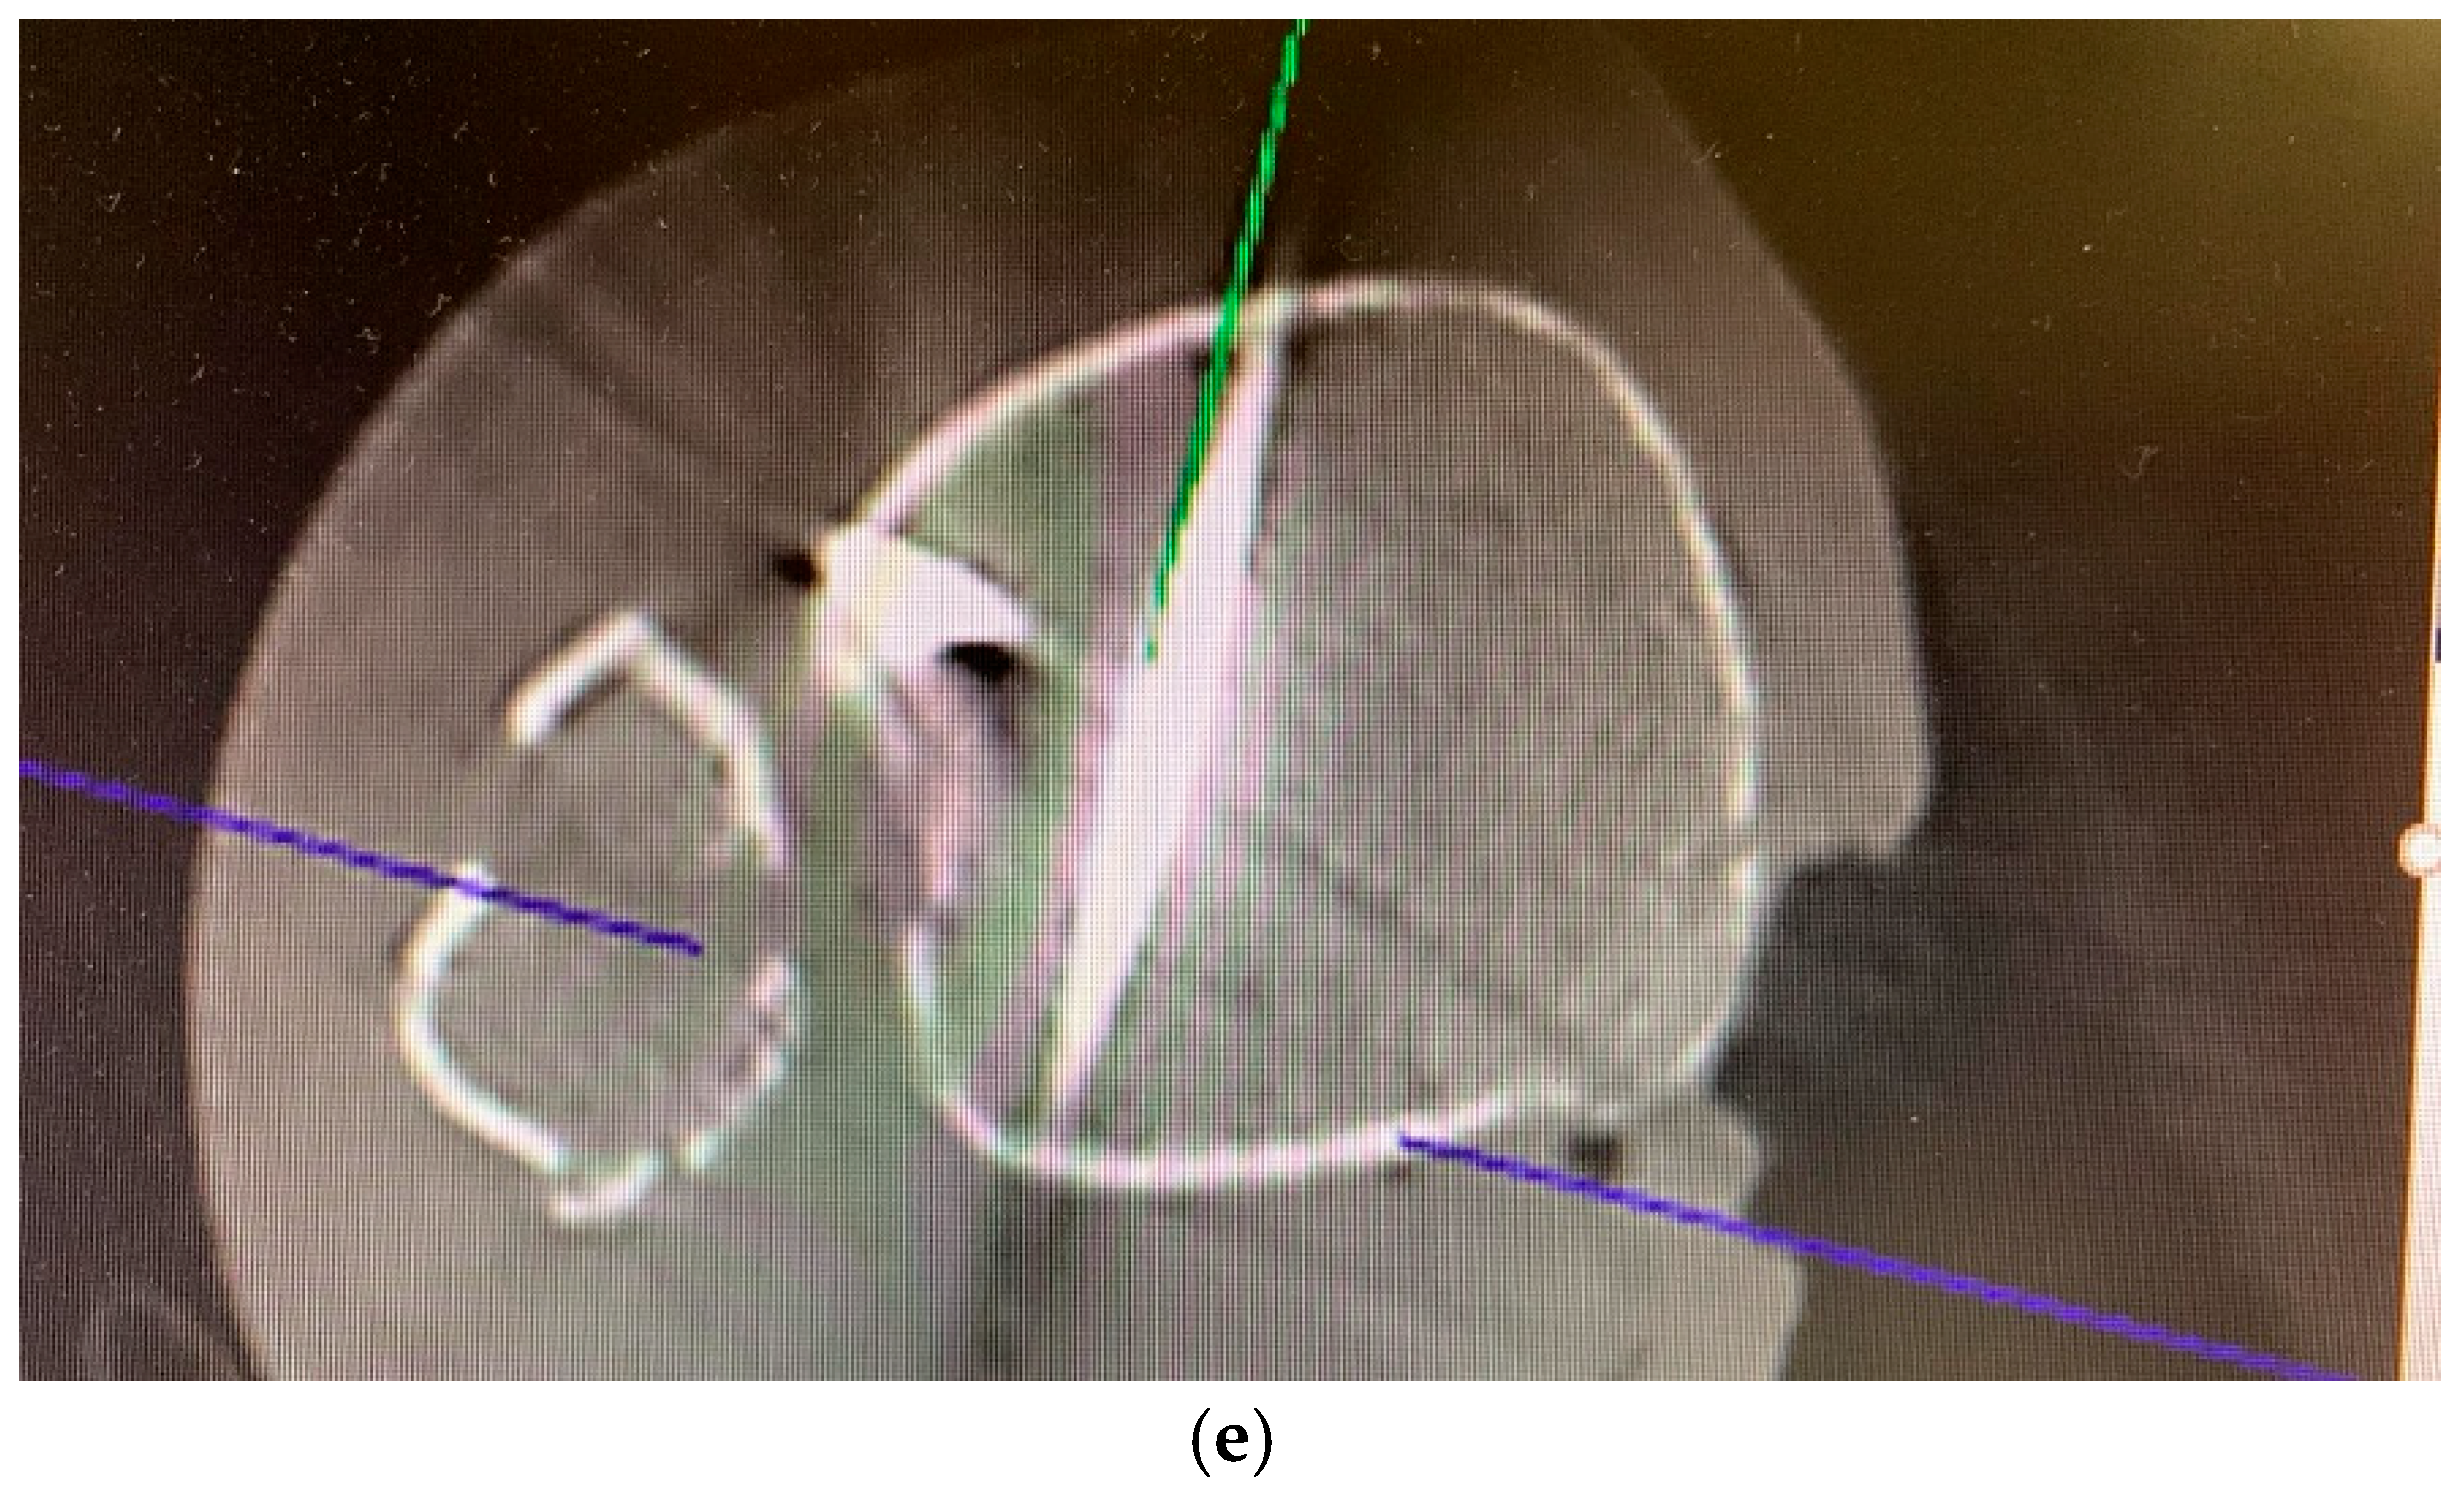

3. Intraoperative 3D Fluoroscopic Control

5.2. Inside-Out Fixation of the Posterior Malleolus Using a Headless Double-Threaded Compression Screw

5.4. Medial Malleolar Cancellous Screw Fixation Using the Modified Posteromedial Approach

5.5. Reamed Intramedullary Locking Nail Fixation of the Distal Fibular Fracture